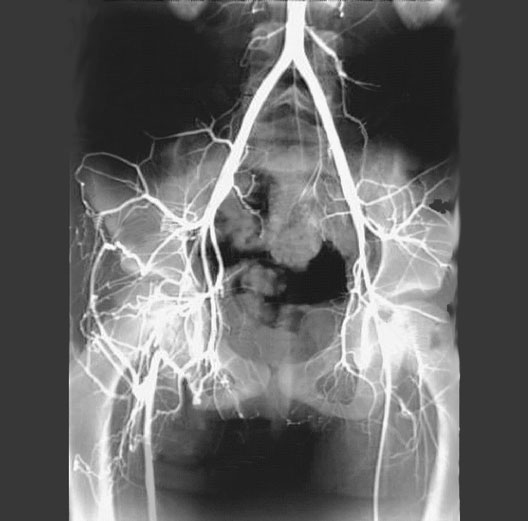

Femoral Artery Occlusion

1. Lumbar artery

2. Right common iliac artery

3. Superior gluteal artery

4. Obturator artery

5. External pudendal artery

6. Right femoral artery

7. Aorta

8. Lumbar artery

9. Median sacral artery

10. Left common iliac artery

11. Iliolumbar artery

12. Left external iliac artery

13. Obturator artery

14. Left femoral artery